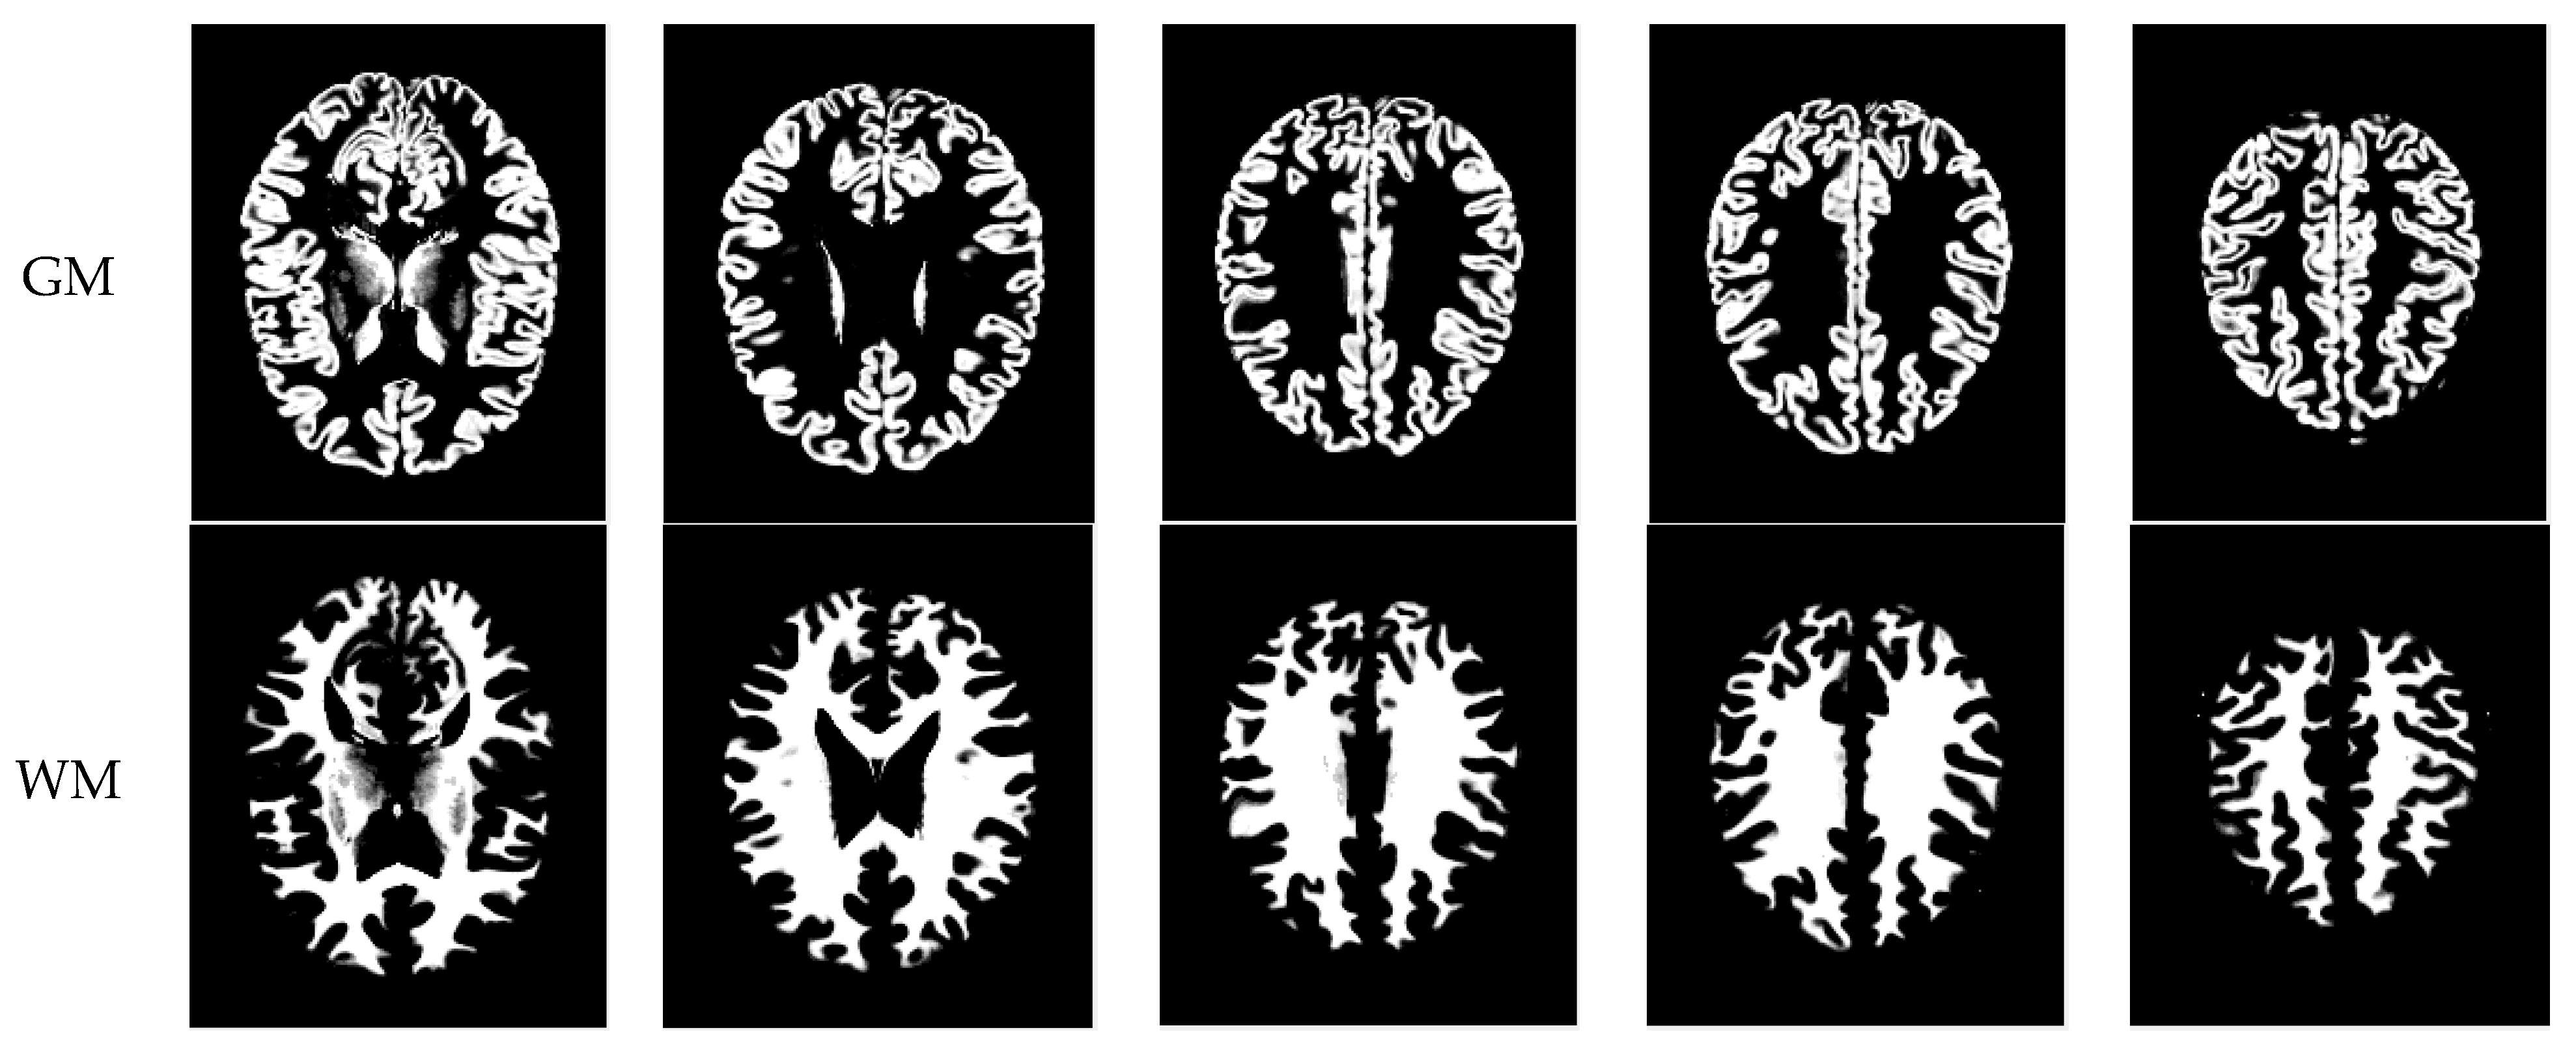

As mentioned before, the images of the first five datasets in Table 3 were used to evaluate the performance of the HMRF-WOA. Figure 1, Figure 2, Figure 3, Figure 4 and Figure 5 show some slices of a T1-weighted image (slices: 84, 95, 105, 108, 120). These brain images correspond to the slices under different types of conditions, such as database type, dimension image, noise level, intensity non-uniformity level, and slice thickness (mm). In Table 1, rows 1 to 5 summarize the parameters of Figure 1, Figure 2, Figure 3, Figure 4 and Figure 5, respectively. Figure 6 represents the ground truth segmentation of slices 84, 95, 105, 108, and 120. In this figure, each column contains the three tissues, GM, WM, and CSF, of each slice. Figure 7, Figure 8, Figure 9, Figure 10 and Figure 11 show the segmentation results, where the four tissues (BG, GM, WM, and CSF) are shown with different colors. The yellow, red, and green colors represent the segmented regions of GM, WM, and CSF, respectively. As we can also see from these figures, the resulting segmented images in Figure 7, Figure 8, Figure 9, Figure 10 and Figure 11 are almost close to the initial images in Figure 1, Figure 2, Figure 3, Figure 4 and Figure 5.

The qualitative analysis provides a visual representation of the segmentation approaches. The visual comparison of the resulting images using the HMRF-WOA appears to be more similar to the reference image (ground truth), where Figure 1, Figure 2, Figure 3, Figure 4 and Figure 5 show the GM, WM, and CSF tissue regions of the reference image with higher values of noise levels (3, 5, 7, and 9%) and intensity non-uniformity levels (20, 40%), whereas Figure 7, Figure 8, Figure 9, Figure 10 and Figure 11 show the subject images obtained using the proposed technique. However, this result shows that with higher values of noise and intensity non-uniformity, the algorithm, with its hyperparameters, is able to segment the tissue regions correctly.

Figure 7. Segmentation results of the slices illustrated in Figure 1.